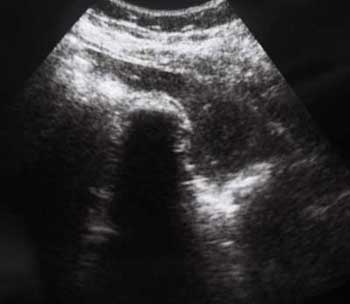

Похожий случай. Молодой мужчина, врач, длительные терпимые боли в правом подреберье.

???

2.По второму случаю можно было бы просто подумать о гиперкинезии ж.пузыря,который сокращается и "от глотка слюны".Но,прочитав эту фразу:"In patients with hilar cholangiocarcinoma and complete obstruction of both rigt and left hepatic ducts,extrahepatic bile ducts and the gollbladder appear empty(colapsed)",учитывая сложность выявления "малых" опухолей печени методом УЗИ,я думаю,что надо сделать КТ.